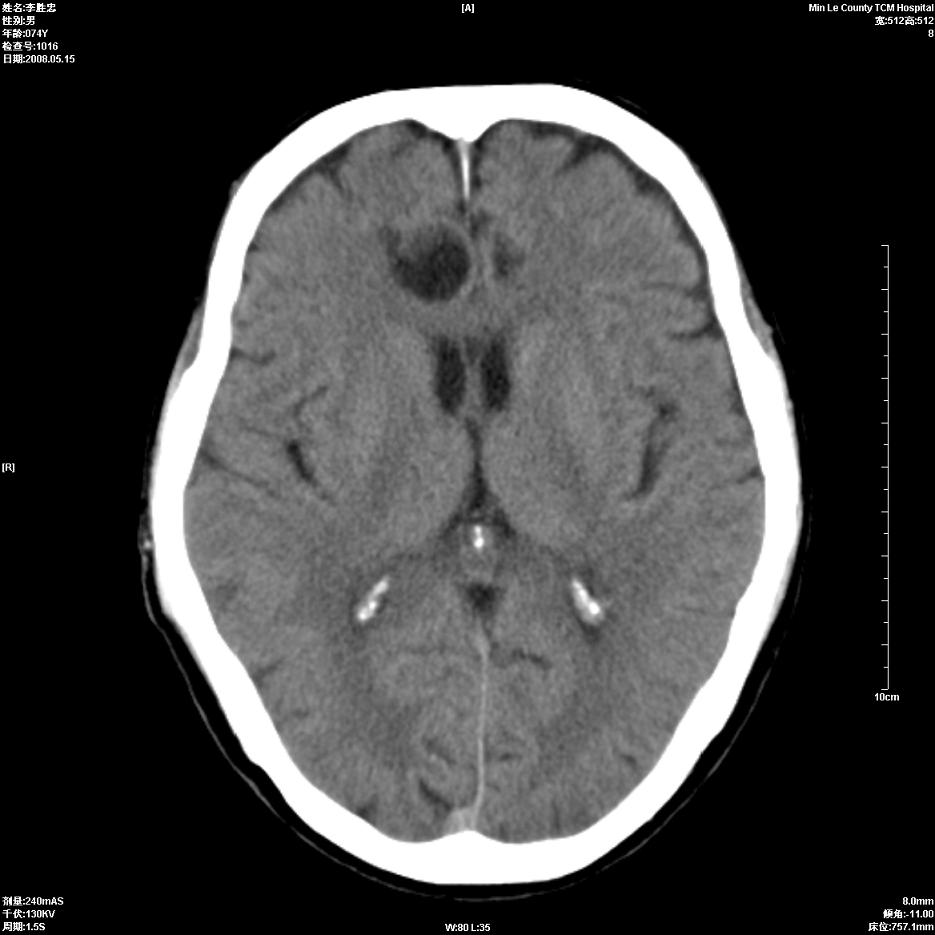

以下是引用hhcckk在2008-5-30 14:26:00的发言:[br]病灶跨中线,有占位效应,强化不明显,考虑胼胝体区低级别的星形细胞瘤可能性大,建议mr检查